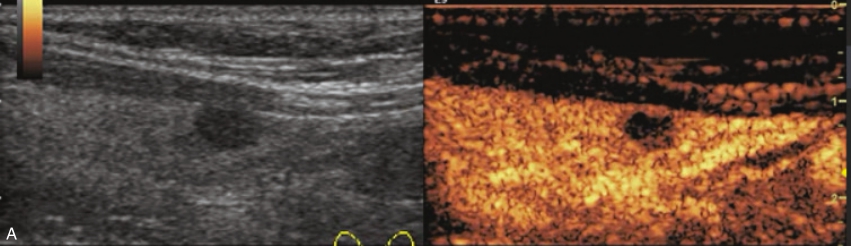

甲状腺囊肿常规超声表现为边界清晰、形态较规则的无回声结节,内可见点状强回声,后伴“彗星尾”征,CDFI内部无明显血流信号,见图1-3-1。

图1-3-1 甲状腺囊肿常规超声声像图

A.甲状腺左叶纵切面;B.CDFI血流图

注入造影剂后结节始终呈无增强,边界清晰,周围腺体呈均匀等增强,见图1-3-2、ER1-3-1。

(1)结节内部始终无造影剂灌注,表现为边界清晰、形态规则的无增强区。

(2)结节周边被膜连续完整。

(3)超声造影可以鉴别单纯囊肿与内部为极低回声的甲状腺实性结节,单纯囊肿造影时内部始终呈无增强,边界清,实性结节在造影过程中可见造影剂灌注,边界不清。